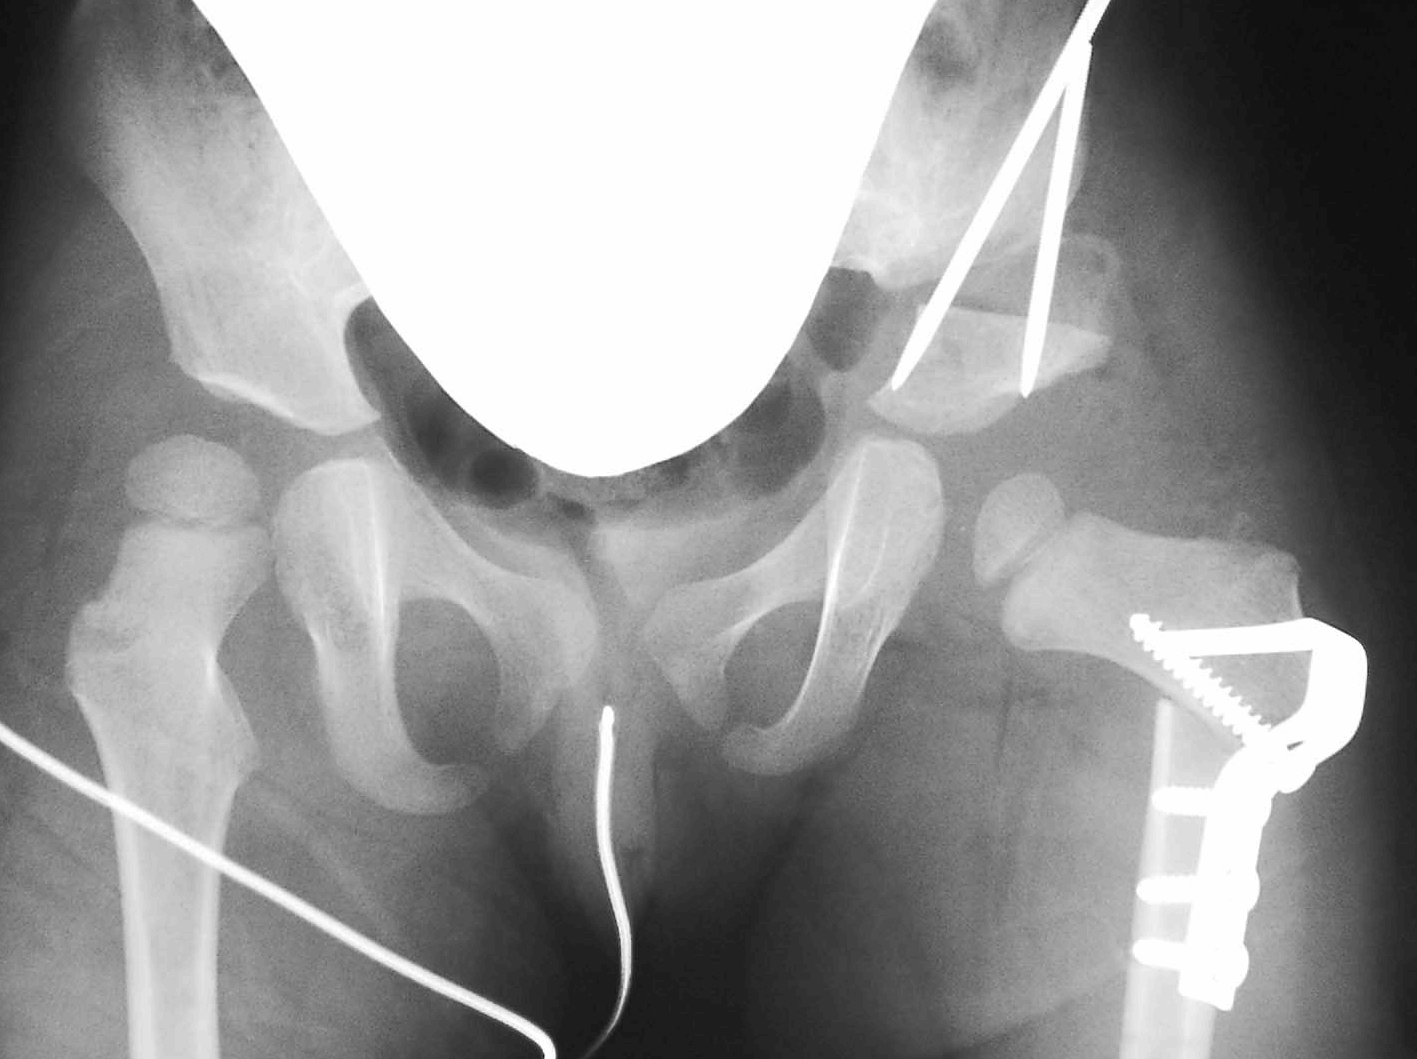

大腿骨切りをおこない、骨頭を臼蓋の中心にに向けたところ。

さらにソルター手術を同時におこなってさらに安定性を与えた。

5歳のX線像。股関節は安定し、歩行はもちろん駆け足も良好である。